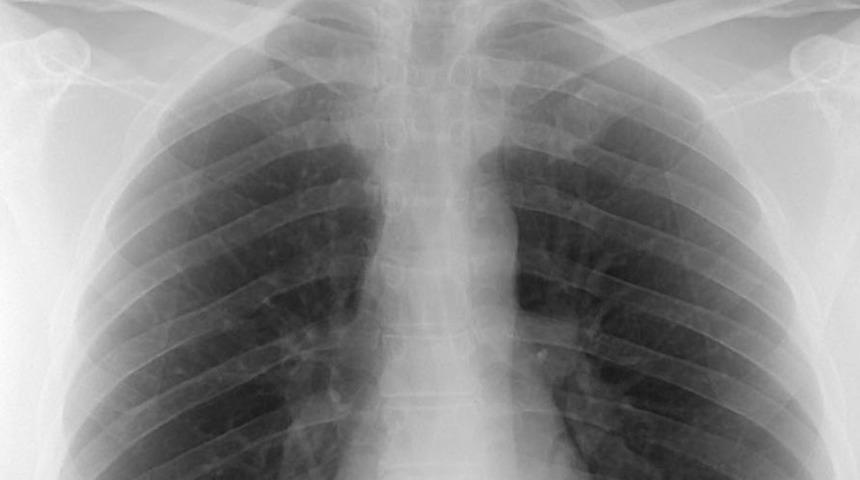

Bir akciğer tomografisinde alınan radyasyon dozunun yaklaşık 300 akciğer filmine eşit olduğu belirtiliyor. Uzmanlar tehliyekeye karşı 'kanser patlar' uyarısında bulunuyor.

Tüm Radyoloji Teknisyenleri ve Teknikerleri Derneği (TÜMRADDER) Başkanı Heybet Aslanoğlu, önlem alınmaması durumunda yakın zamanda kanser vakalarının artacağına dikkat çekerek "Bir akciğer tomografisinde alınan radyasyon dozu yaklaşık 300 akciğer filmine eşittir. Gereksiz yere tomografi çekilen hastalar (özellikle çocuklar) kanser riski ile karşı karşıya kalıyor. Önlem alınmazsa yakın zamanda kanser vakaları artacak ve radyoloji üniteleri faciaya dönüşecek" uyarısında bulundu.